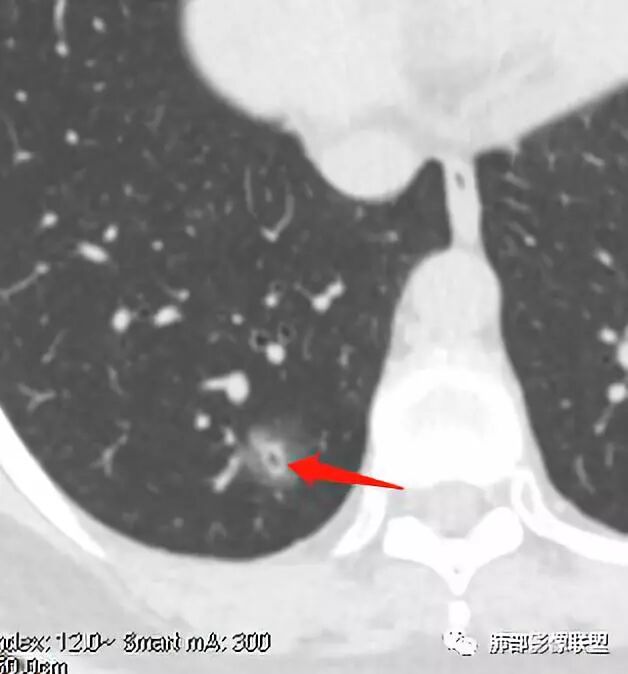

南边:

52岁男性,恶性的好发年龄,炎性也可以。

扫描是薄层。

连续层面显示这个应该是空泡,或者小空洞,远端没有,近端也没有,周围环形软组织增厚。而空泡,影像上只是根据5mm界线,病理上不一定。

问一个问题,肺动脉肺静脉?为啥?

静脉,夹角90,周边没气管伴行。

静脉吧,动脉同时会伴有一根气管

这些呢?为啥?

动脉,有支气管伴行

伴有支气管

假如这是含气支气管,伴随的哪条动脉呢?近端从哪来?为啥环形壁增厚而又不均匀?都不太符合,所以支持空泡或小空洞。

上次刘纯老师提出,空泡征是一个影像征象,不是一个病理征象,我比较支持,他就是一个影像上的小低密度腔,原因很多,但是影像上与小的空洞表现区分不了。其中的原理:有一条是内容物排出后的残腔,其实也是空洞的原理。

大家考虑恶性的依据?炎性的依据?首先这是不是磨玻璃结节?依据是啥?

因为密度比肺组织高,但是又遮盖不了血管,所以GGO明确

是pGGO?mGGO?

实性的部分超过10%——mGGO

GGO边缘清不清?依据?

部分清,部分不清

依据:能不能沿GGO边缘画出一个边界

能否勾勒出边界?是否有血管?

排除血管的边缘,边界清吗?

可惜的是背景也模糊了一些

患者后来到上海做了手术,电话回访告知结果为粘液腺癌